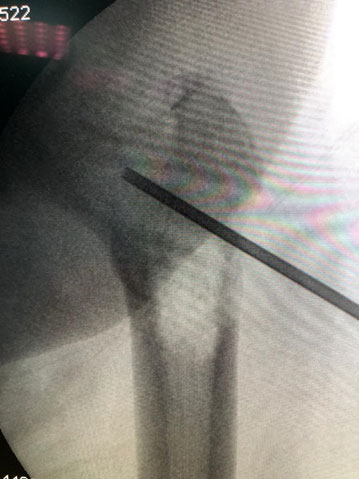

Biyopsi: Skopi (seyyar röntgen) eşliğinde kapalı iğne biyopsisi uygulanımı